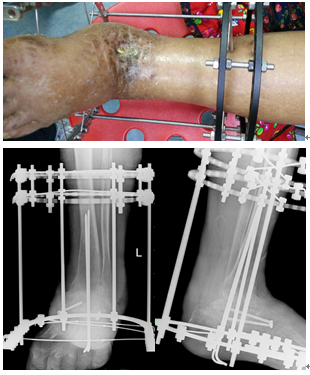

术前:

术后: